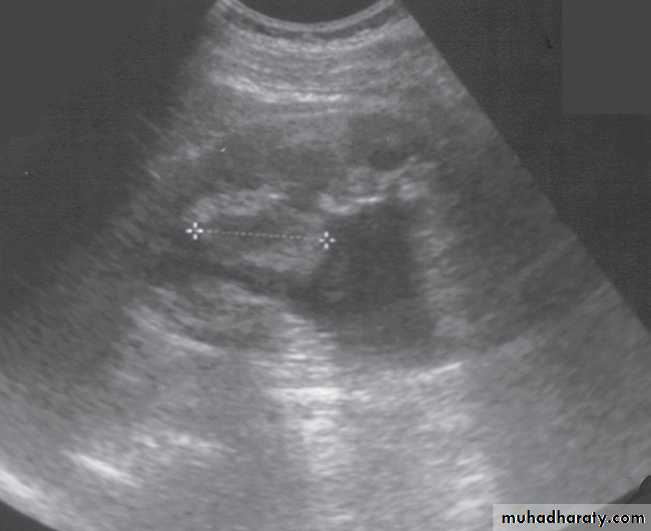

Ultrasound Dilatation of the pelvicaliceal system ( hydronephrosis ) is demonstrated sonographically as a multiloculate fluid collection in the central echo complex, caused by pooling of urine within the distended pelvis and calices .

Major DDX are multiple renal cysts. With prolonged obstruction, thinning of the cortex due to atrophy will be seen.

Renal masses are usually first detected at ultrasound examination.Ultrasound can establish whether a mass is a simple cyst and can, therefore, be ignored, or whether the lesion is solid and, therefore, is likely to be a renal carcinoma.( further evaluation with CT is indicated ) .

-A mass with mixed cystic and solid features falls into the indeterminate category and could be a renal tumour, a renal abscess, or possibly a complex benign cyst or other benign condition ( also further evalution with CT scan is indicated )